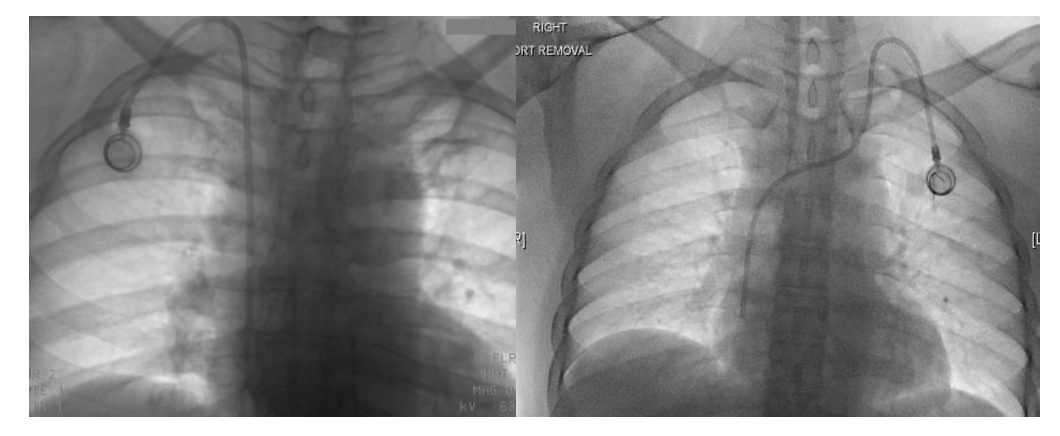

Fifteen patients (1.48%, 0.041/1000 catheter days) developed catheter dysfunctions (11 thrombotic and 4 nonthrombotic). Only 1 out of 11 thrombotic dysfunctions developed early, which occurred after 27 catheter days. The patient developed catheter occlusion, which was proven on a patency check done in the IR suite. Five out of 11 ports were explanted (port removal for fibrin sheath formation shown in Figure 4) and the remaining 6 were successfully treated with thrombolysis with urokinase (Figure 5). The thrombotic complication with fibrin sheath formation occurred as late as 1206 days, which was treated with thrombolysis using urokinase.

There were 3 catheter migrations and 1 port rotation. Catheter migrations (Figure 4) were noticed to migrate into the right IJV, right brachiocephalic vein, and left subclavian vein. All these patients underwent explantation and reinsertion of the ports. One of the patients whose port was migrated to the right IJV was admitted for chemoport removal and reinsertion. However, during the manipulation of the displaced port catheter, she began experiencing severe rigors in the IR suite. She was afebrile and hemodynamically stable; the procedure was abandoned, the port removed, and the patient shifted to the ward immediately. Cultures were drawn and she was started on I.V. cefoperazone-sulbactam, along with teicoplanin. She went into septic shock that evening and I.V. cefoperazone-sulbactam was changed to injected. Meropenem at a 2-g loading dose was followed by 1 g every 8 hours. She was resuscitated with fluids and remained hemodynamically stable afterward. One port rotation in the chest wall was incidentally detected on a follow-up computed tomography (CT) scan of the chest, but the patient had already completed chemotherapy so no treatment was sought.